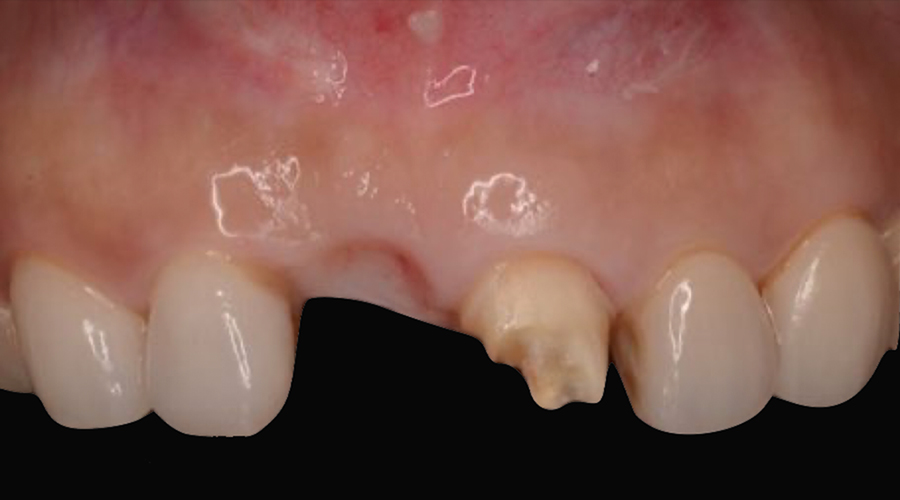

- 治療内容

- 欠損部位に対して、人工歯根を埋入し上部構造として補綴物をかぶせる治療です。

- 治療に伴うリスク

- 治療後の口腔管理が不適切な場合、埋入したインプラント周囲に感染・炎症を起こし、脱落する可能性がございます。